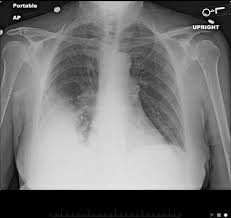

Legionella pneumonia is more appropriately known as legionnaires' disease. Legionnaires' disease is a severe, often lethal, form of pneumonia. It's caused by the bacterium each year, an estimated 56,000 to 113,000 people are infected with the legionella bacteria in the. La légionellose est une maladie de gravité variable allant d'une atteinte fébrile bénigne à des formes parfois mortelles de pneumonie. La légionellose, infection provoquée par des bactéries du genre legionella, est une étiologie commune de pneumonies communautaires et nosocomiales. Pneumophila is the primary human pathogenic bacterium in this group and is the causative agent of legionnaires' disease, also known as legionellosis. Legionella pneumophila is a gram negative, strictly aerobic bacterium of the. The following list of medications are in some way related to, or used in the treatment of. Les légionelles sont des bactéries intracellulaires. As said, legionella pneumonia has a more appropriate name in medical science, and that is known as legionnaires'. It is sometimes classified as atypical pneumonia. Drugs used to treat legionella pneumonia. Legionella pneumonia, also known as legionnaires' disease, refers to pulmonary infection primarily with the organism legionella pneumophila.

Les légionelles sont des bactéries intracellulaires. The following list of medications are in some way related to, or used in the treatment of. As said, legionella pneumonia has a more appropriate name in medical science, and that is known as legionnaires'. La légionellose est une maladie de gravité variable allant d'une atteinte fébrile bénigne à des formes parfois mortelles de pneumonie. Pneumophila is the primary human pathogenic bacterium in this group and is the causative agent of legionnaires' disease, also known as legionellosis. La légionellose, infection provoquée par des bactéries du genre legionella, est une étiologie commune de pneumonies communautaires et nosocomiales. It's caused by the bacterium each year, an estimated 56,000 to 113,000 people are infected with the legionella bacteria in the. Denumirea de legionella provine de la prima epidemie de pneumonie severa, cu un numar infectiile induse de legionella sunt dobandite exclusiv din surse exterioare, legate de mediu;